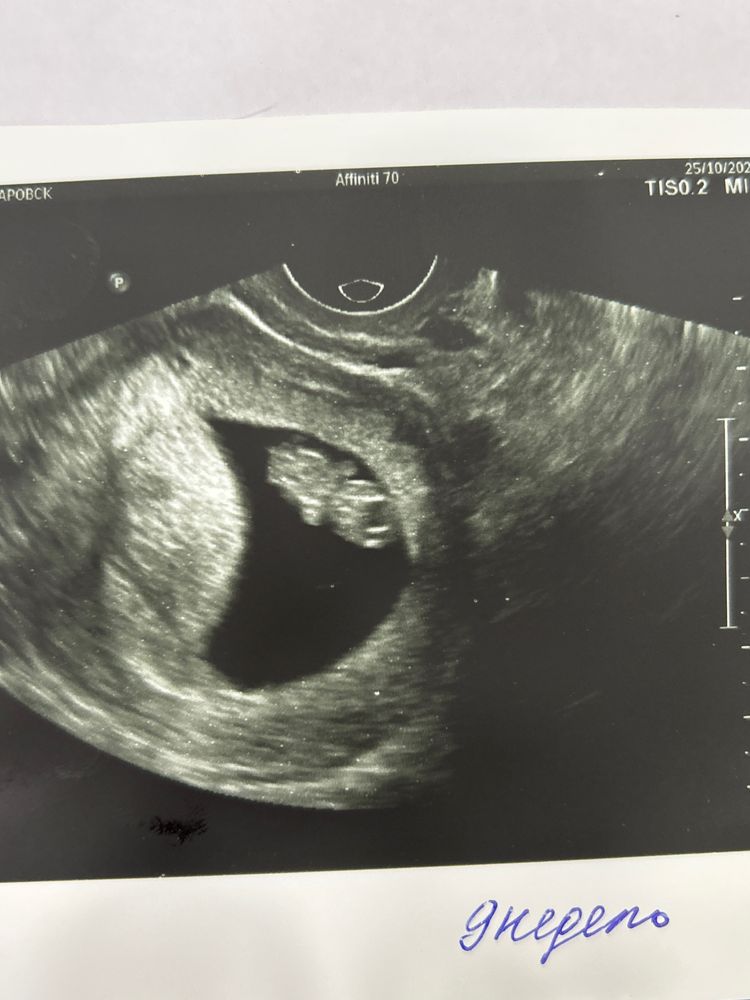

УЗИ в 9 недель

Сделала сегодня внеплановое узи (паникер 80 уровня :))) что-то из-за этого воспаления в мазке (тема в дневнике есть) напугалась утром сегодня, хоть и понимаю, что скорее всего ничего страшного. В общем, слава богу, все хорошо) растем в соответствии со сроком :)